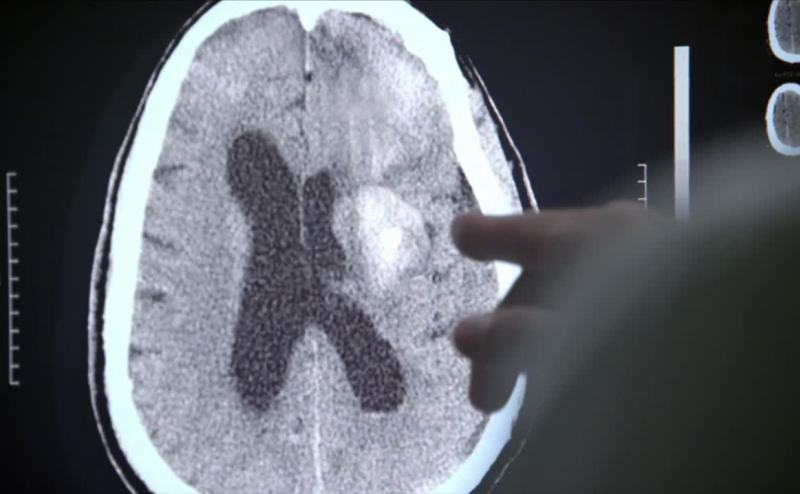

Large occlusion... there. Lot of plaque.

Middle cerebral artery, swelling.

Need hemicraniectomy.